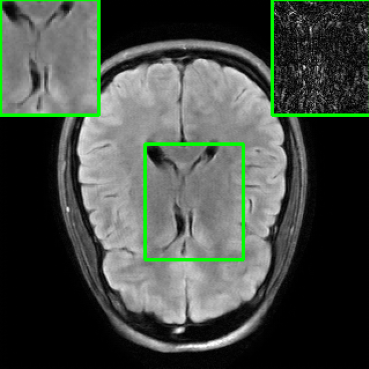

5.4 Visualizations

We now present visual samples from both the knee and brain datasets. Specifically, Figure 5 presents visual comparison of image reconstructions and their associated reconstruction errors within a closely examined region. Each image in the figure includes two inset panels in the top-left and top-right corners. The top-left inset panel, enclosed within a green bounding box, serves as a reference for the region of interest in the image. In contrast, the top-right inset panel depicts an error map in relation to the ground truth. Notably, our method stands out in its ability to capture the original image’s features, surpassing the performance of alternative methods (as also evident from the reported PSNR values). This visual comparison underscores the superior quality and accuracy of our approach in the robustification of the MRI image reconstruction task.